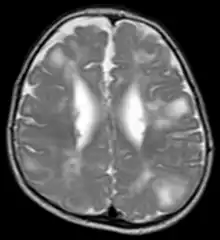

TSC in MRI

Classic intracranial manifestations of TSC include subependymal nodules and cortical/subcortical tubers.[6]

The tubers are typically triangular in configuration, with the apex pointed towards the ventricles, and are thought to represent foci of abnormal neuronal migration. The T2 signal abnormalities may subside in adulthood, but will still be visible on histopathological analysis. On magnetic resonance imaging (MRI), TSC patients can exhibit other signs consistent with abnormal neuron migration such as radial white matter tracts hyperintense on T2WI and heterotopic grey matter.

Subependymal nodules are composed of abnormal, swollen glial cells and bizarre multinucleated cells which are indeterminate for glial or neuronal origin. Interposed neural tissue is not present. These nodules have a tendency to calcify as the patient ages. A nodule that markedly enhances and enlarges over time should be considered suspicious for transformation into a subependymal giant cell astrocytoma, which typically develops in the region of the foramen of Monro, in which case it is at risk of developing an obstructive hydrocephalus.[7]

A variable degree of ventricular enlargement is seen, either obstructive (e.g. by a subependymal nodule in the region of the foramen of Monro) or idiopathic in nature.